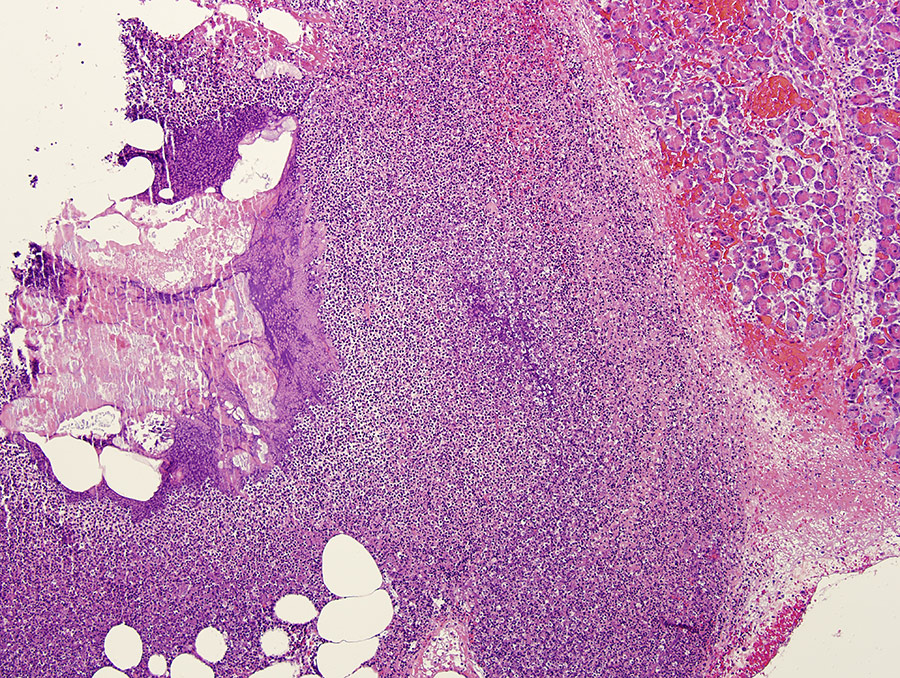

Shelley J Newman博士以兽医病理学和教育知识为名,自2000年以来,她大部分工作都与得克萨斯A&M大学胃肠实验室联手完成,今天继续,因为她是该校附属教授,诊断内分片生物检测服务队成员,博士生委员会成员最引人注意的工作环绕警犬MCT的病理特征MCT是最常见肿瘤之一,影响不同年龄狗的皮肤(剖析性),但Boxers、BostonTriers和Weimar诊断时大都带单质量狗3-14%的病例多团 — — 约50%的肿瘤恶性化,特别是在老式易处理品种中。多因子决定预测性,但肿瘤的语理学类(组织研究)非常重要。肿瘤分级总需要组织学检验,因为它有助于更精确预测行为,细胞学尚未完全实现

Newman生涯的大部分时间里 Patnaik评分系统是唯一使用系统Newman与Patnaik博士合作四年,2000年代初期在纽约动物医疗中心工作Patnaik分级系统与更新双级Kiupel分级系统同时使用,用于骨架分级并判定警犬MCT预测Patnaik系统根据各种因素,包括细胞形态学和入侵性,将警犬MCT划分为三级等级I完全有别MCT特征是良好的长期预测,可通过外科手术有效处理二级中等差分三级MCT差分并更有可能传播这使得外科控制不成功

原Patnaik分级系统不包括MCT子切变异Newman使用扩散细胞核抗原和新分子技术,率先描述MCT子变异的病理学并识别临床结果狗类子变异多功能观察较少攻击性,中间语义级扩展平均生存时间-结果更好长期预测完全基于皮肤内部位置扩散标记,包括Ki67/PCNA/Agnor/c-Kit分数,过去曾发现这些分数有助于帮助剖析和评分相近MCT,与MCT子值分数有正相关关系。自那以来,进一步研究扩展到肿瘤群并识别增强诊断标准